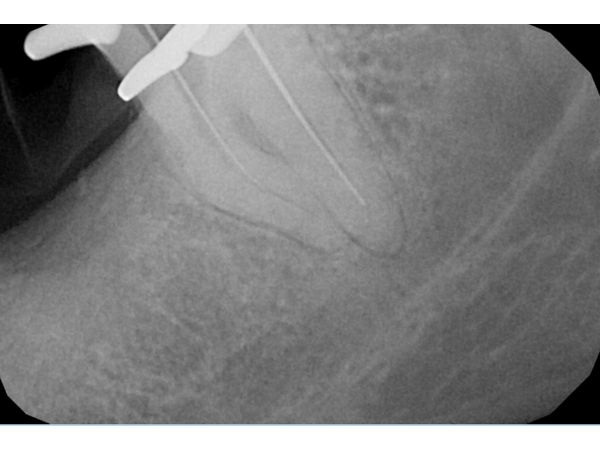

Под контролем апекслокатора, который определяет длину корневого канала, женщине полностью очистили дистальный канал и обработали его до верхушки. Так как ход медиальных каналов не просматривался из-за проведённого ранее вмешательства, медиальные каналы остались необработанными.

Микроскоп показывал ход каналов только до изгиба, но предварительное изучение анатомии зуба с помощью КТ и достаточный опыт позволили найти медиально-язычный и медиально-щёчный каналы вручную. Их длину подтвердил апекслокатор.